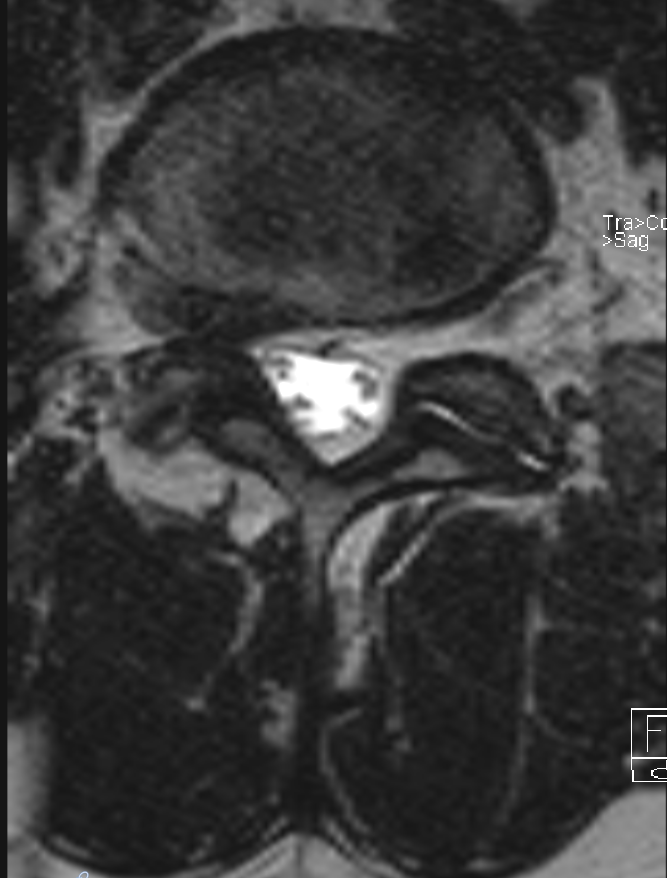

Intraforaminaler Bandscheibenvorfall im MRi

Darstellung eines axialen T2 MRI Bildes eines Patienten mit einem intraforaminalen Bandscheibenvorfall LWK3/4 auf der linken Seite.